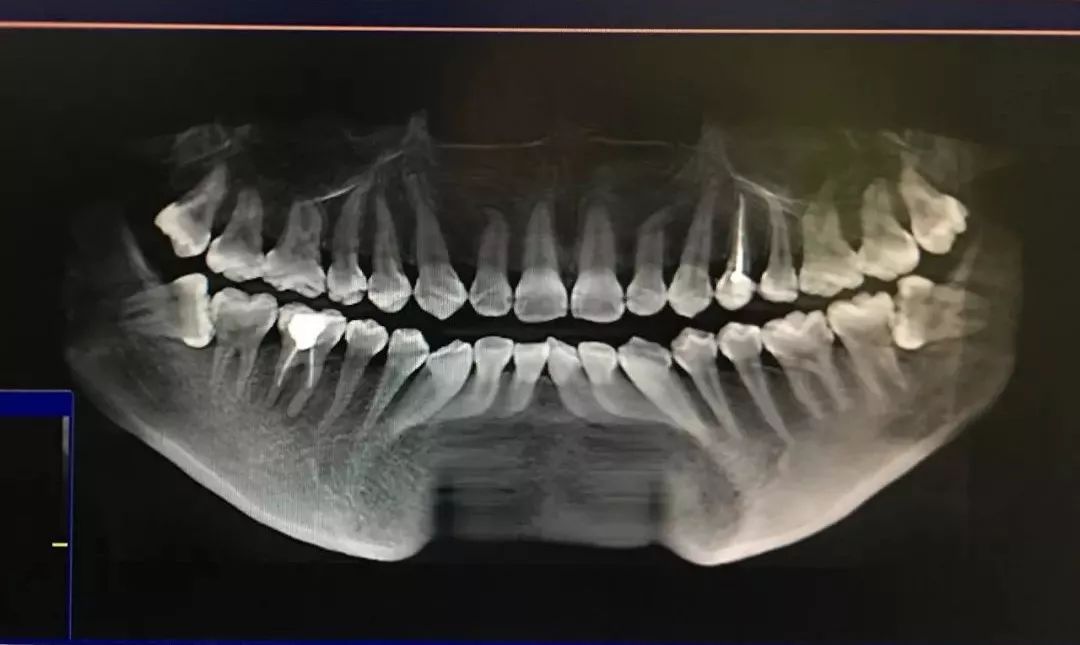

在门诊上,我们医生首先要通过全景片来判断智齿拔除的难度然后给出

拔智齿拍全景片有什么好处?

如果你的全景片上,智齿也是这样紧紧地"依偎"着7号牙(最后一颗磨牙)